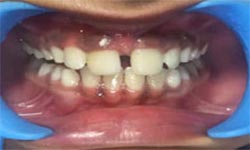

(7) Clinical Case-Veneer

Before Treatment

After Treatment

This female patient, with age 28 yrs came with a complaint of dirty teeth and an unaesthetic tooth in upper front left side of mouth. The patient has been treated with a thorough oral prophylaxis followed by veneering of the tooth.